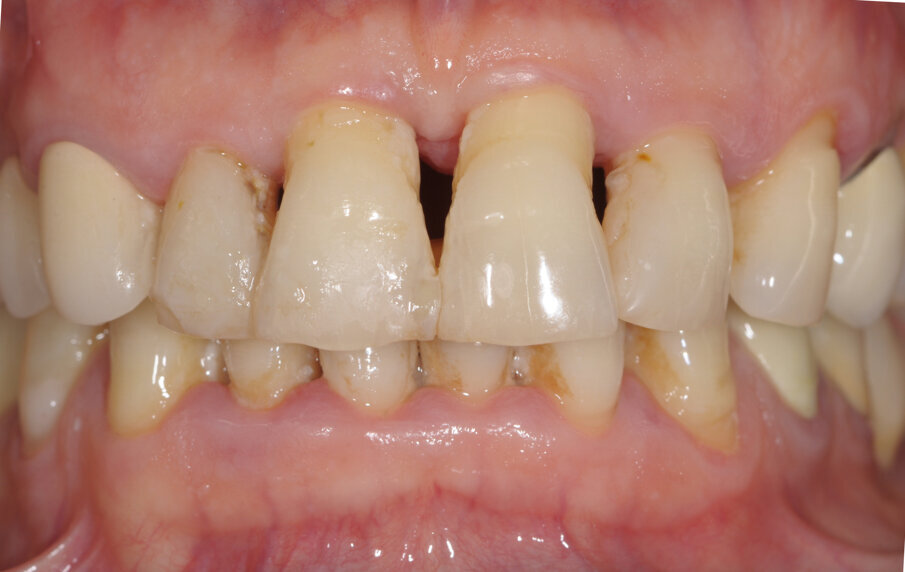

Paziente di sesso femminile, 56 anni, affetta da malattia parodontale cronica con annessa perimplantite in zona 36. La paziente è allergica alla clorexidina ed in oltre riferisce una non tolleranza ideologica per le cure chimico-farmacologiche in genere.

A termine del trattamento descritto in precedenza da un punto di vista clinico abbiamo ottenuto un ripristino dei parametri di salute dell’impianto ovvero la scomparsa del sanguinamento dell’edema e della purulenza, in oltre si è verificata una riepitelizzazione dei tessuti molli limitrofi l’impianto. Da un punto di vista radiografico abbiamo ottenuto la neoformazione di osso attorno alle spire dell’impianto (con relativo aumento della stabilità) che a inizio terapia era da considerarsi potenzialmente come perso. La radiografia a 60 gg prima ed a 1 anno mostrano quanto prima descritto, ovvero un ripopolamento di componenti cellulari ossei sull’impianto con un recupero di 3 spire implantari (Figg. 7-9).